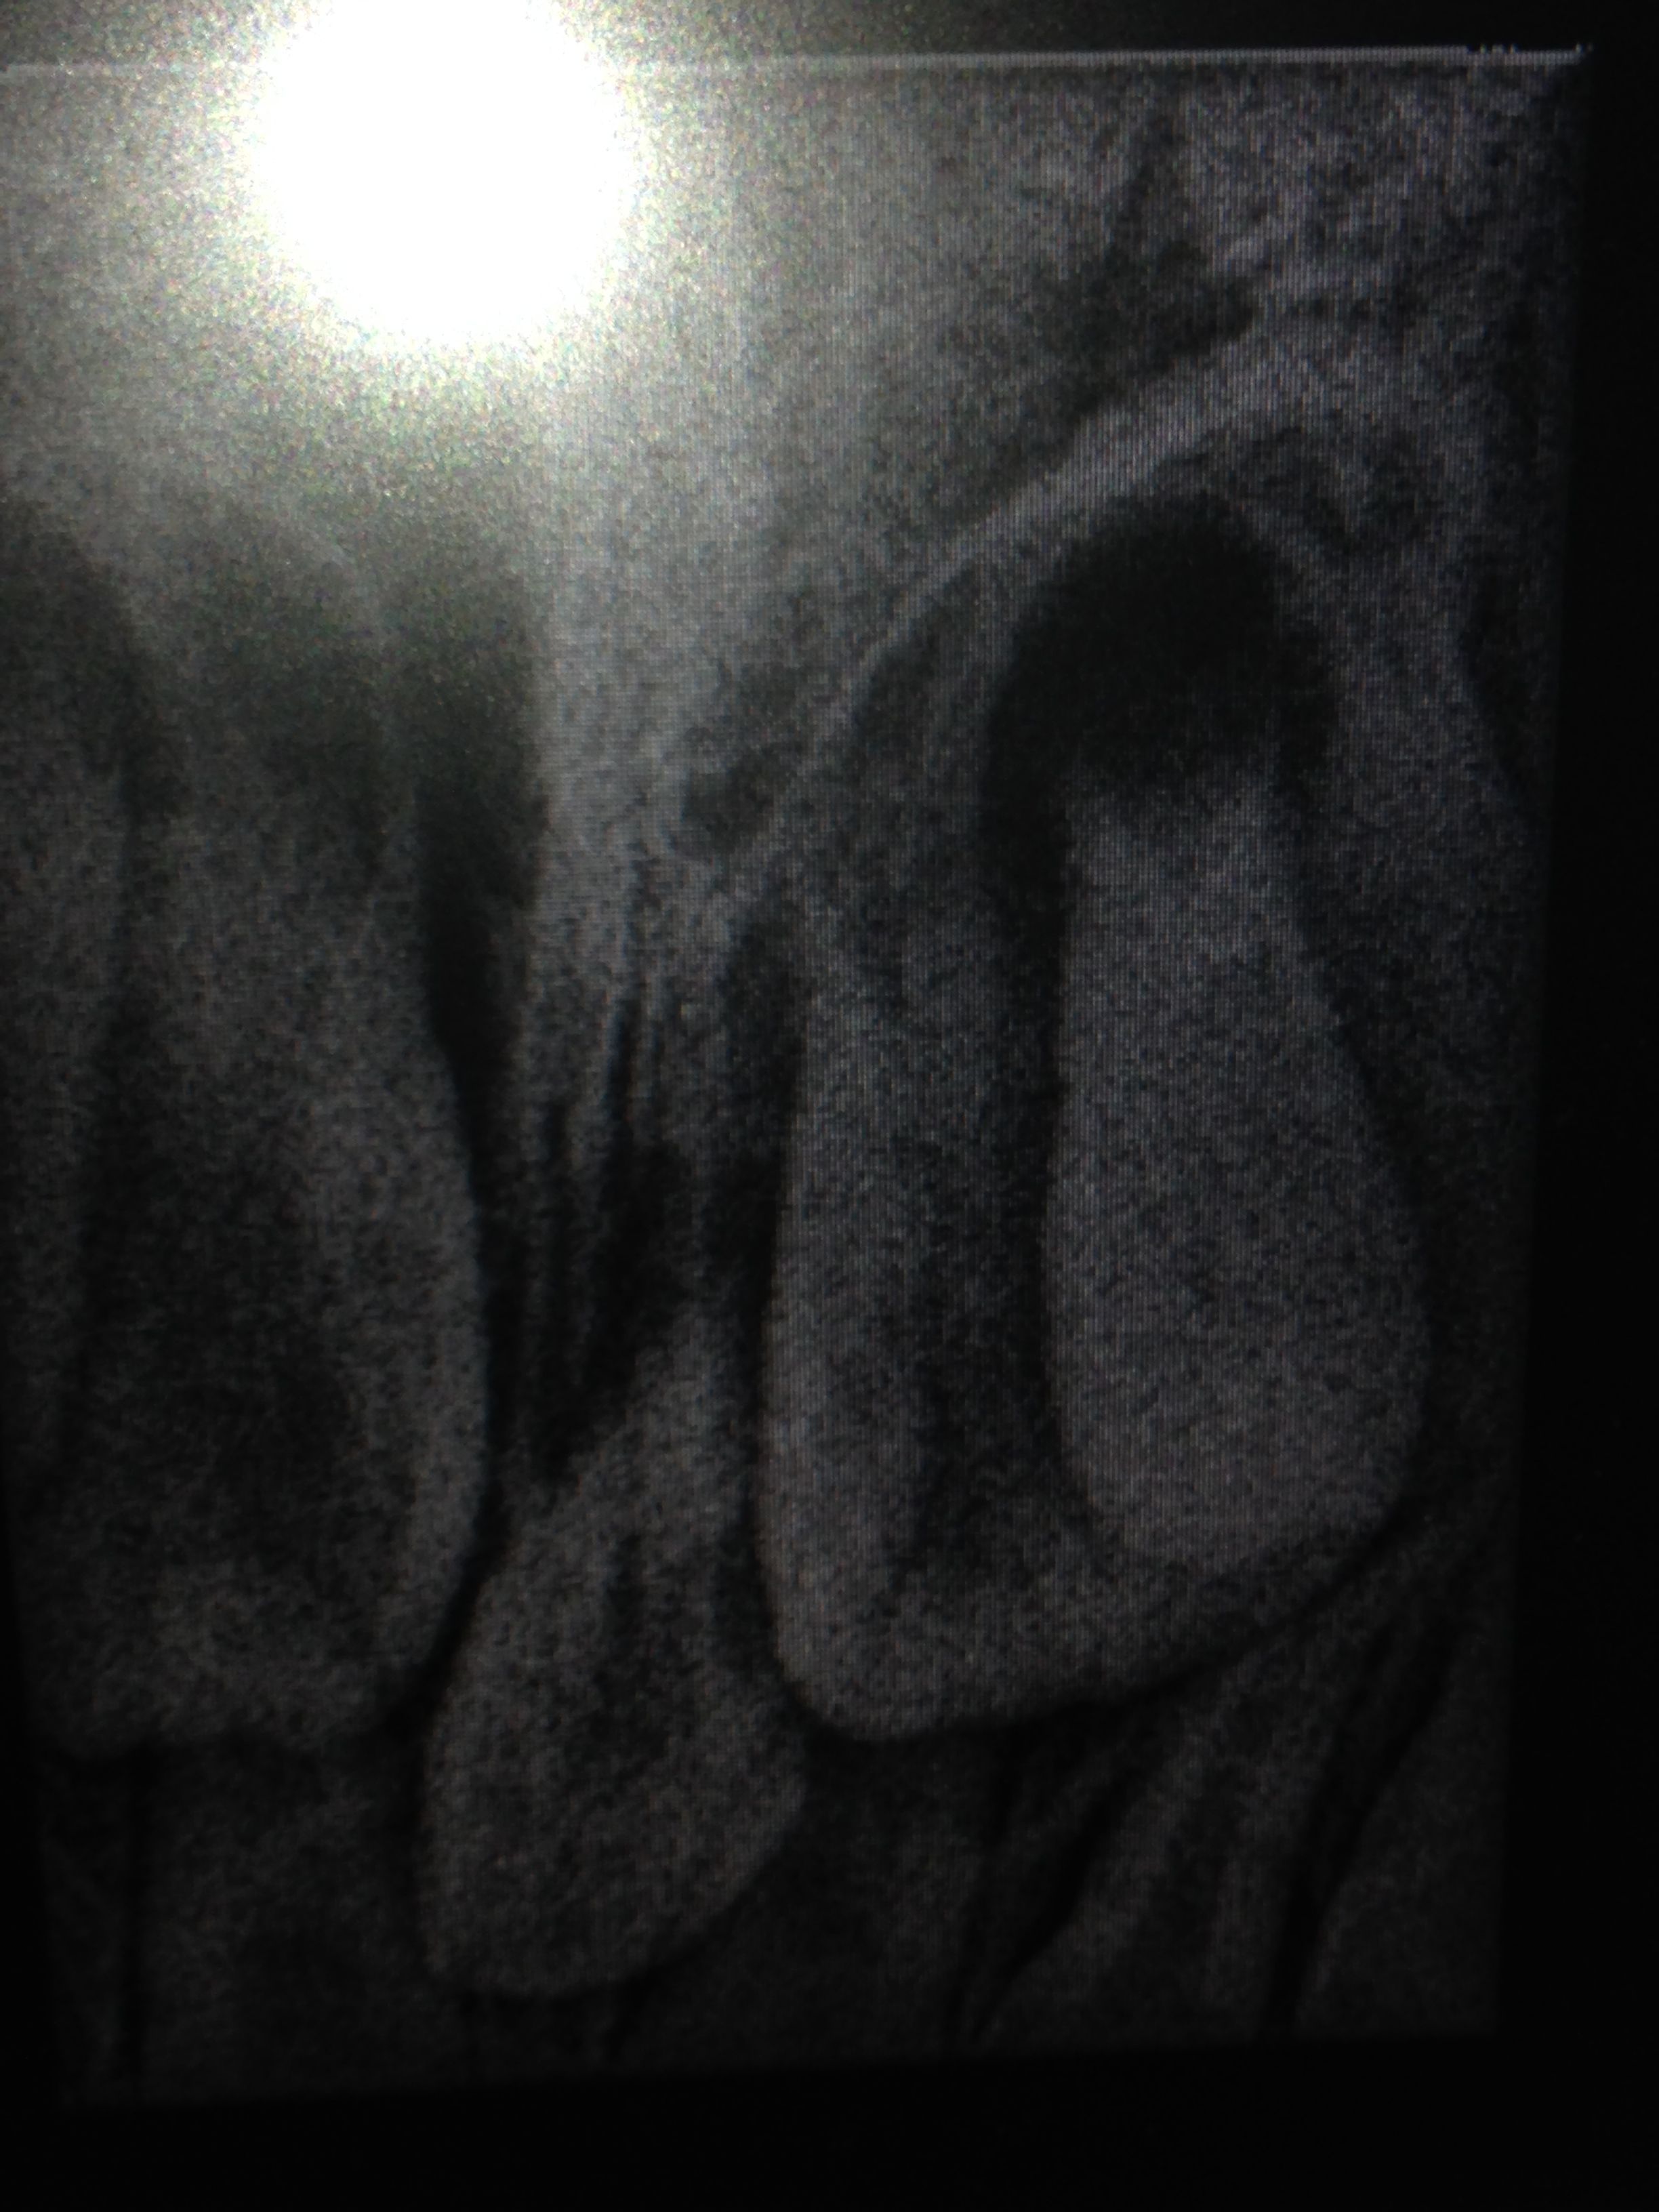

小孩5岁半,门牙后长了牙齿,乳牙还没松动,怎么办?医生说是多生牙? 点击展开 匿名用户 2014-12-15 08:56 为您推荐: 其他回答 你好,你这是长智齿,是正常的,对你的生活没有什么影响的 建议你到专科口腔医院或诊所的颌面外科进行检查,如果位置正常的话就没事的,如果位置不正的话,这颗牙齿需要拔除,要不然很容易长蛀牙,也不好清洁 刘东医生 2014-12-16 10:13 相关问题 我家儿子六岁了,他的下门牙(乳牙)还没掉也没有松动,可是牙齿里面又长了一颗牙,怎么办? 牙齿裂成两半还能补吗?小孩玩不小心摔倒了,门牙裂成两半,现在的是乳牙来的 有没医生在…为什么我生完小孩后牙齿没以前好使了